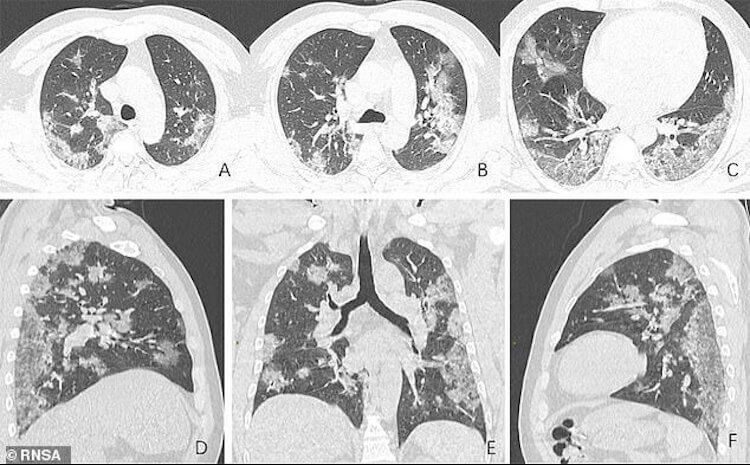

Сам коронавирус не может привести к болезням, требующим пересадку легких. Правда, есть информация, что вирус, вызывая воспалительные процессы, может безвозвратно повредить до 20 процентов легких. Даже если болезнь протекает бессимптомно.

Обычно даже при таком повреждении не требуется пересадка легких. Но некоторые воспаления и развившаяся пневмония может привести к необходимости в такой операции. Правда, такая вероятность очень низкая. По крайней мере, пока. Вообще, вероятность умереть от последствий пневмонии есть и от них в мире умирает больше людей, чем от инфаркта миокарда. Такие смерти вызваны не самой пневмонией, а септическим шоком, который поражает другие органы и системы.